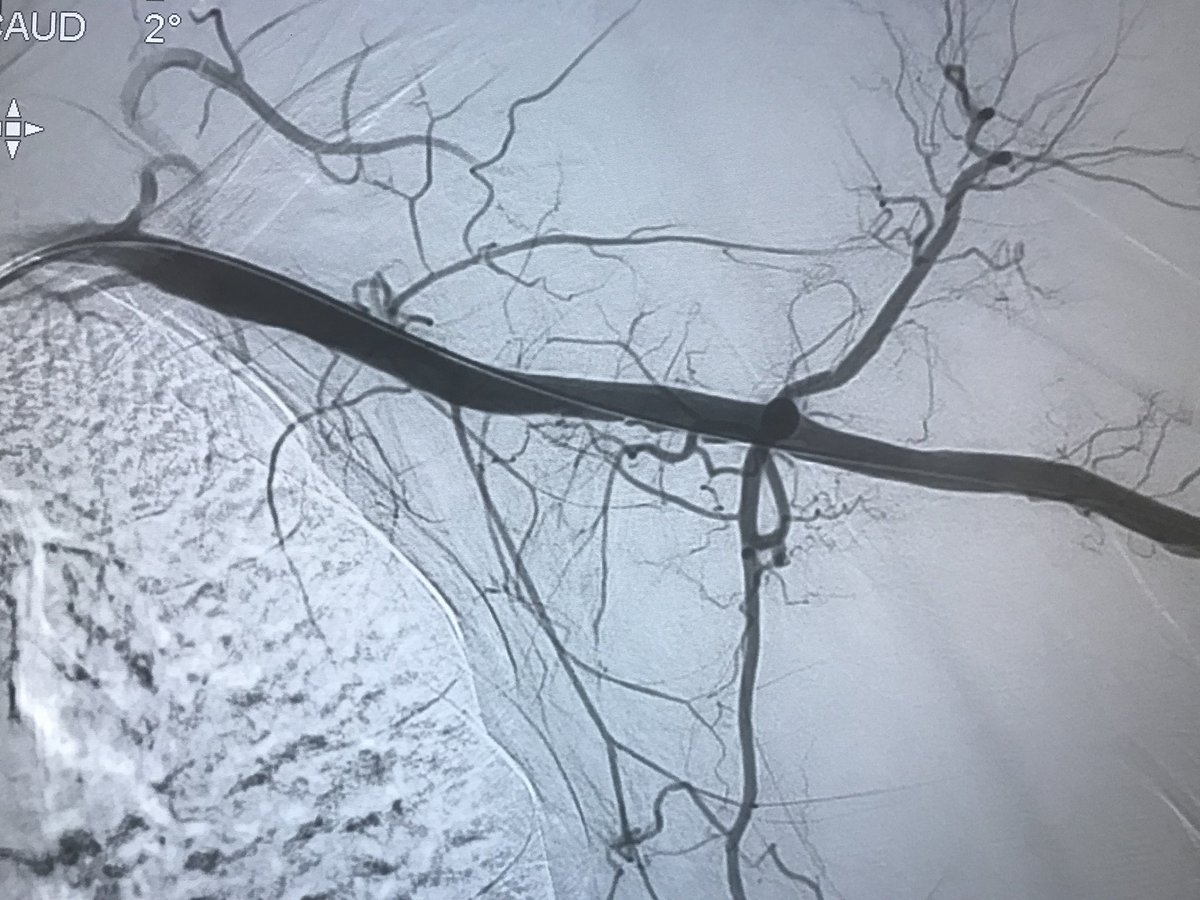

62 y/o male presents with NSTEMI. Boarded for cath in am. Prior to cath VT arrest and on vasopressors Findings at cath, severe LAD, CTO LCx, CTO RCA. LVEDP 34mmhg, EF 10%. Severe PAD. Rx with IC fellow sticks #PercAx Impella and IVUS guided revasc. Now off vasopressors.

DrAmirKaki's tweet image. 62 y/o male presents with NSTEMI.  Boarded for cath in am.  Prior to cath VT arrest and on vasopressors Findings at cath, severe LAD, CTO LCx, CTO RCA.  LVEDP 34mmhg, EF 10%.  Severe PAD.  Rx with IC fellow sticks #PercAx Impella and IVUS guided revasc.  Now off vasopressors.